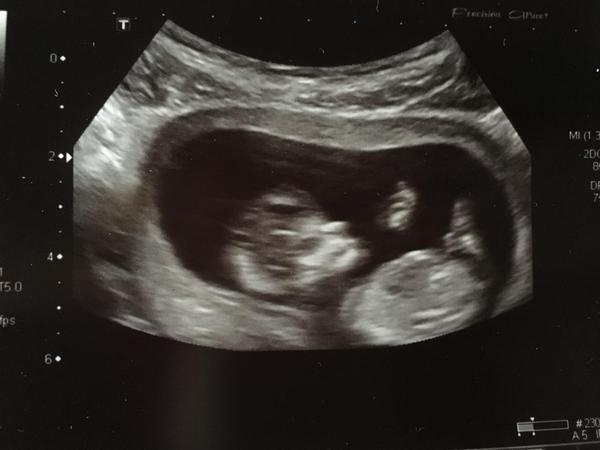

Pohlaví dle ultrazvuku

Těžko říct, tady mi to přijde trochu vychýlené. Tak možná kluk? Ale ono to i od doktora je teď ještě jen na 80%

@miaelle90 myslím si, že holka. Pohlavni hrbolek moc není vidět, ale bylo mi vysvětleno, že pokud je vodorovně s páteří, je to holka. Pokud je maličko vychýlený, tak chlapeček. Sedělo mi to u obou dcer.